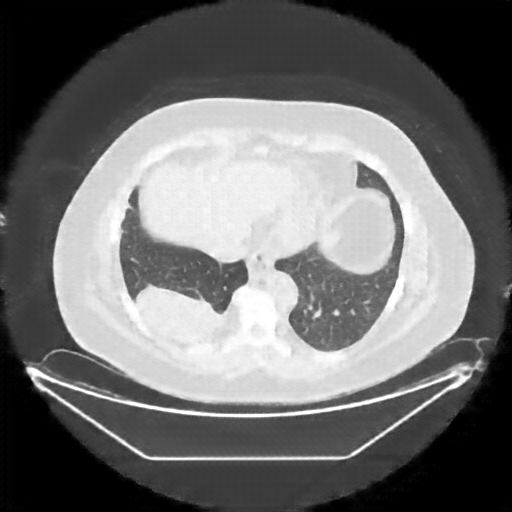

Generated VENOUS CT scan (A→B translation)

No window - Raw intensity values

Lung window (WL -600, WW 1500 β†’ Low βˆ’1350, High +150)

Mediastinum window (WL 40, WW 400 β†’ Low βˆ’160, High +240)